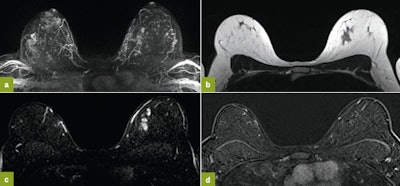

First MRI screening of a 37-year-old patient, carrier of the gene mutation BRCA 1 during the 22nd day of her cycle. An asymmetrical background matrix enhancement effect potentially masking a, b, c. Close monitoring on the 10th cycle day (d) allows validation of the classification BI-RADS 2. Image courtesy of JFR.

Information provided by the patients is essential and allows us to obtain their cooperation and also ensures adherence to further exams or complementary biopsies. Other than indications for an extended assessment of proven cancer where delay to therapy start must be taken into account, MRI must be scheduled where physiological matrix enhancement effect is minimal, either in the second week of the menstrual cycle for premenopausal patients or after stopping thyroid-stimulating hormones.